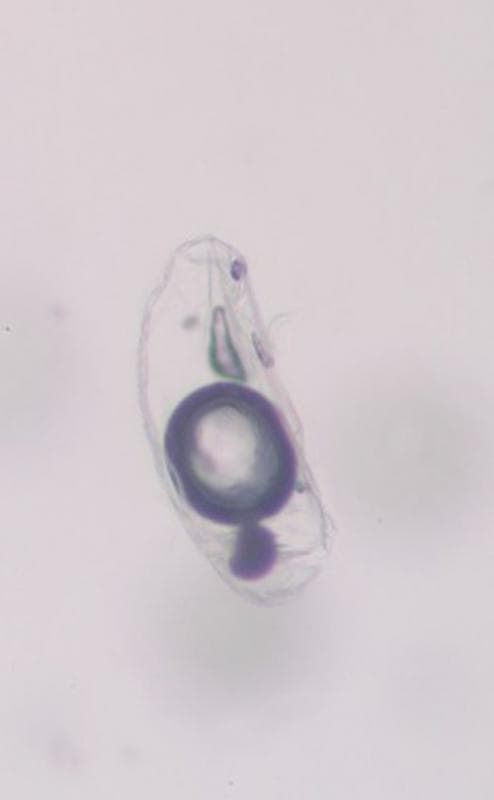

Un simple brossage, ainsi qu’un test à la cellophane adhésive suivi d’une observation microscopique sans coloration, permettent la visualisation d’une population uniforme de nombreux parasites, à tous les stades évolutifs (Photos 4 et 5). L’examen à un fort grossissement nous conduit à identifier Cheyletiella parasitivorax, ectoparasite commun du lapin.

du produit de brossage : mise en évidence d’œufs et de cheylétielles adultes